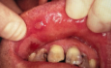

PRIMARY HERPETIC GINGIVOSTOMATITIS

CLINICAL FEATURES:

rarely occurs before 6 months

short, yellowish, fluid-filled vesicles develop